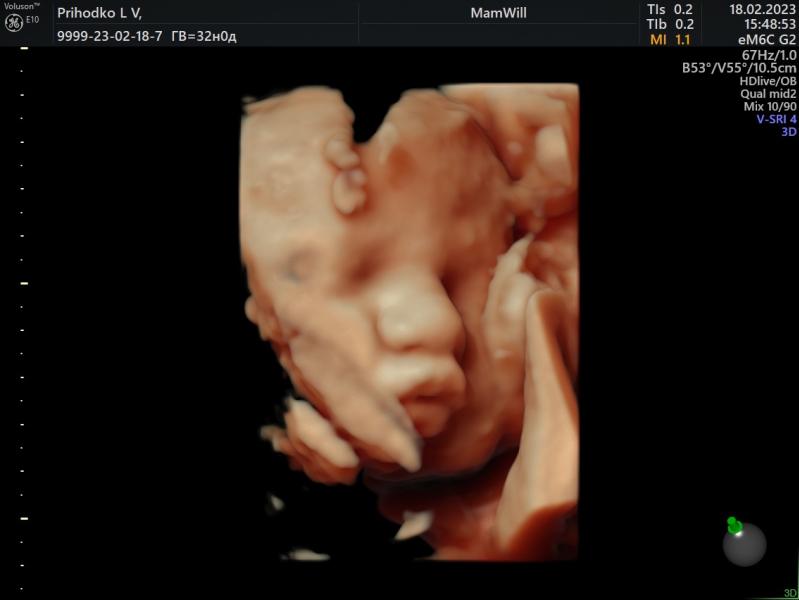

Мой губастенький мальчик не хочет переворачиваться(

Сидим в тазовом